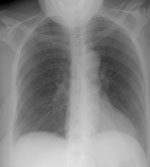

Vascular AbnormalitiesVascular > PE > Images > Saddle EmbolismScott WilliamsApr 2, 2002Saddle Pulmonary Embolism: The case below demonstrates an example of saddle embolism (white arrows) Latest in Vascular AbnormalitiesVascular > PAHOctober 19, 2020Vascular > Giant cell_Temporal arteritisFebruary 22, 2010Vascular > PE > Images > Right heart strainNovember 15, 2007Vascular > Trapped lungMay 30, 2007Related StoriesVascular AbnormalitiesVascular > ChronicPE > Images > Case2Vascular AbnormalitiesVascular > Aorticaneurysm > Images > Ascending with aortic stenosisVascular AbnormalitiesVascular > Pulmedema > Images > High altitudeVascular AbnormalitiesVascular > Dissection > Images > TypeA > Case2